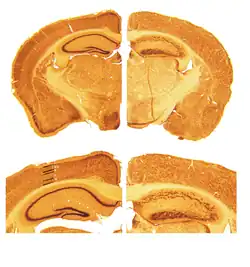

![]() |

Мышь, названная reeler, была впервые описана в 1951 году британским генетиком Дугласом Скоттом Фальконером.[12] В 1960-е годы было обнаружено, что мозжечок у этих мышей намного меньше нормы, к тому же нарушена нормальная организация нейрональных слоёв.[13] Мутация особенно заинтересовала исследователей после того, как было обнаружено, что слои нейронов у мышей выстраиваются «наоборот»: более молодые нейроны были не состоянии преодолеть слои уже «осевших» на своем уровне клеток.[14]